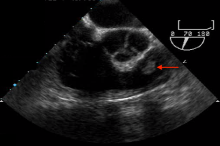

A 56-year-old Caucasian male presented with exertional dyspnea, occasional palpitations, and night sweats. He underwent transthoracic echocardiography, which suggested a possible pulmonic valve tumor. A follow-up transesophageal echocardiography demonstrated a freely mobile, well circumscribed, nearly 1 cm tumor on the anterior leaflet of an otherwise structurally normal pulmonic valve (Figure 1 [4]). Contrast chest CT was remarkable for bilobulated tumor of the pulmonic valve consistent with a PFE (Figure 2 [5]).